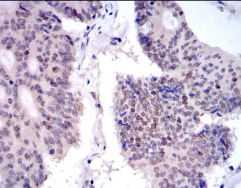

KID Mouse Monoclonal antibody[1E3E1]

IHC    1/200 - 1/1000